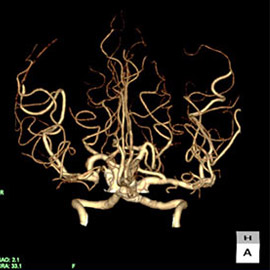

80列マルチスライスCT 検査 画像例

80列マルチスライスCTで撮影した画像

心臓(冠動脈)

主に狭心症や心筋梗塞などの診断